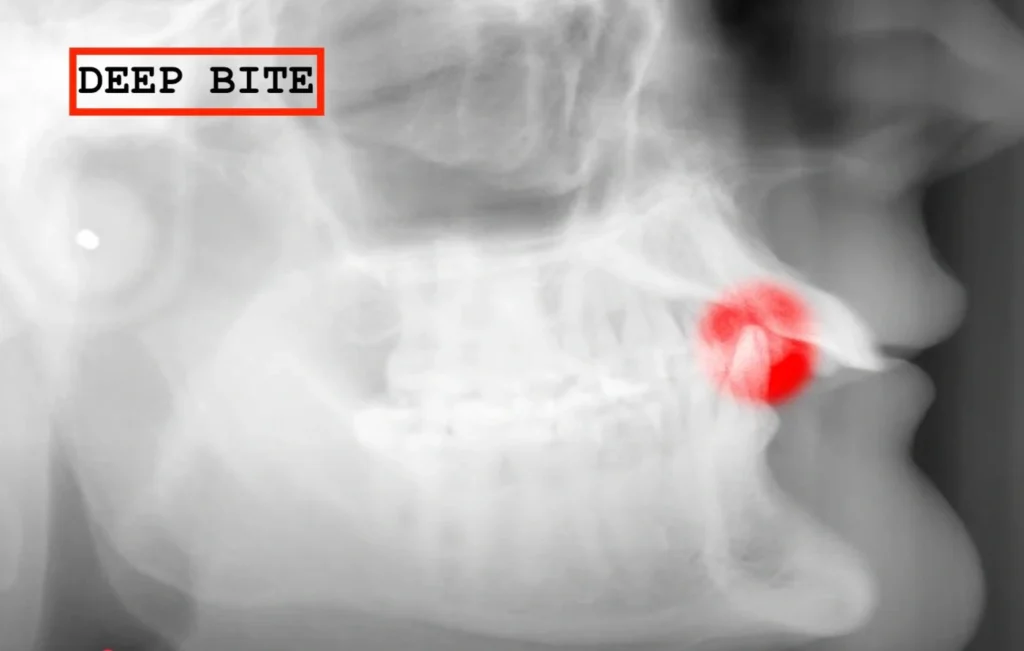

1. The Deep Bite: When Your Child’s Teeth Don’t Line Up Right

One of the most common problems I see is a deep bite.

This is a vertical issue where the upper teeth overlap the lower teeth so much that you can’t even see the bottom teeth.

Why should you worry? If a deep bite goes unaddressed, the teeth don’t meet properly. This misalignment can cause severe wear and tear on the teeth over time, eventually leading to tooth breakage and even tooth loss. I’ve treated many adults who came in with worn-down teeth due to untreated deep bites.

Here’s a visual example of what this looks like:

Patient Example #2: A more severe case where untreated deep bites led to significant tooth wear and difficulty chewing.